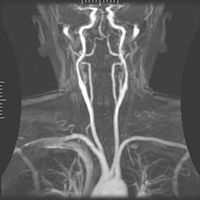

[edit] Magnetic resonance angiography

Magnetic Resonance Angiography

Magnetic resonance angiography (MRA) is used to generate pictures of the arteries in order to evaluate them for stenosis (abnormal narrowing) or aneurysms (vessel wall dilatations, at risk of rupture). MRA is often used to evaluate the arteries of the neck and brain, the thoracic and abdominal aorta, the renal arteries, and the legs (called a "run-off"). A variety of techniques can be used to generate the pictures, such as administration of a paramagnetic contrast agent (gadolinium) or using a technique known as "flow-related enhancement" (e.g. 2D and 3D time-of-flight sequences), where most of the signal on an image is due to blood which has recently moved into that plane, see also FLASH MRI. Magnetic resonance venography (MRV) is a similar procedure that is used to image veins. In this method the tissue is now excited inferiorly while signal is gathered in the plane immediately superior to the excitation plane, and thus imaging the venous blood which has recently moved from the excited plane.